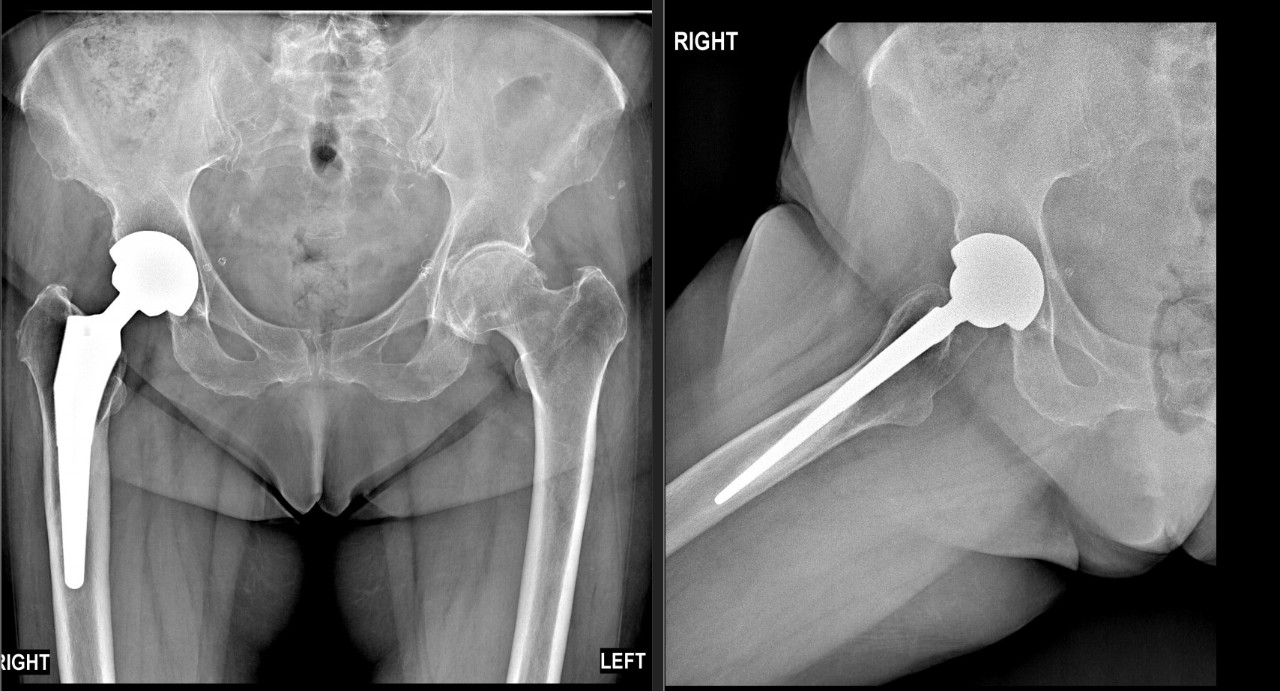

У пациента в анамнезе — эндопротезирование тазобедренного сустава и разная длина ног. Это привело к нарушению биомеханики и перегрузке КПС — того самого сустава, который соединяет таз с крестцом. Именно его дисфункция давала знакомую боль.

У второго пациента при осмотре был положителен тест FADIR (боль при сгибании, приведении и внутренней ротации бедра). Рентген подтвердил диагноз: импинджмент-синдром. Из-за выраженных дегенеративных изменений в тазобедренном суставе - шейка бедра «соударяется» с краем вертлужной впадины, вызывая боль и мышечно-тонический синдром.